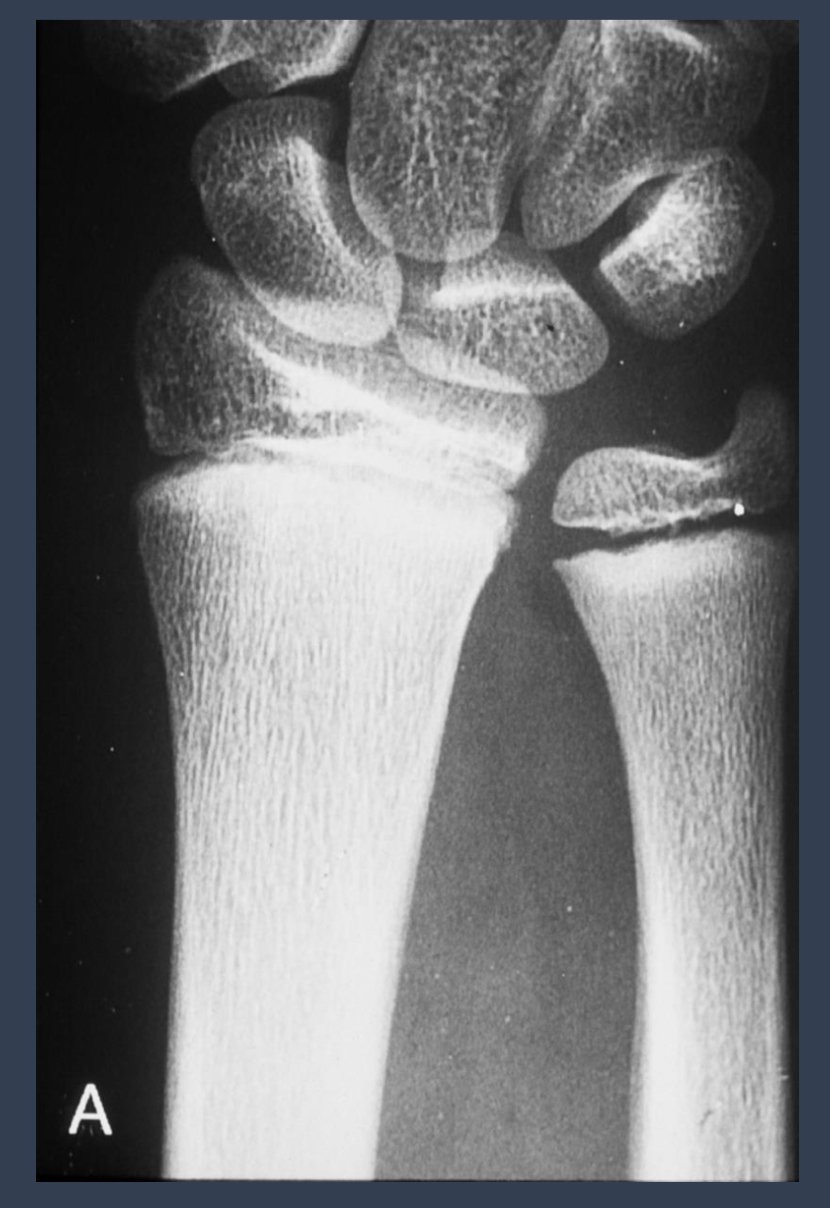

what are the arrows pointing to?

sequestrum = island of dead bone

photo: same patient, repeat xrays

what condition is this?

osteomyelitis

what is the left? what is the right

left: acute osteomyelitis

right: chronic osteomyelitis